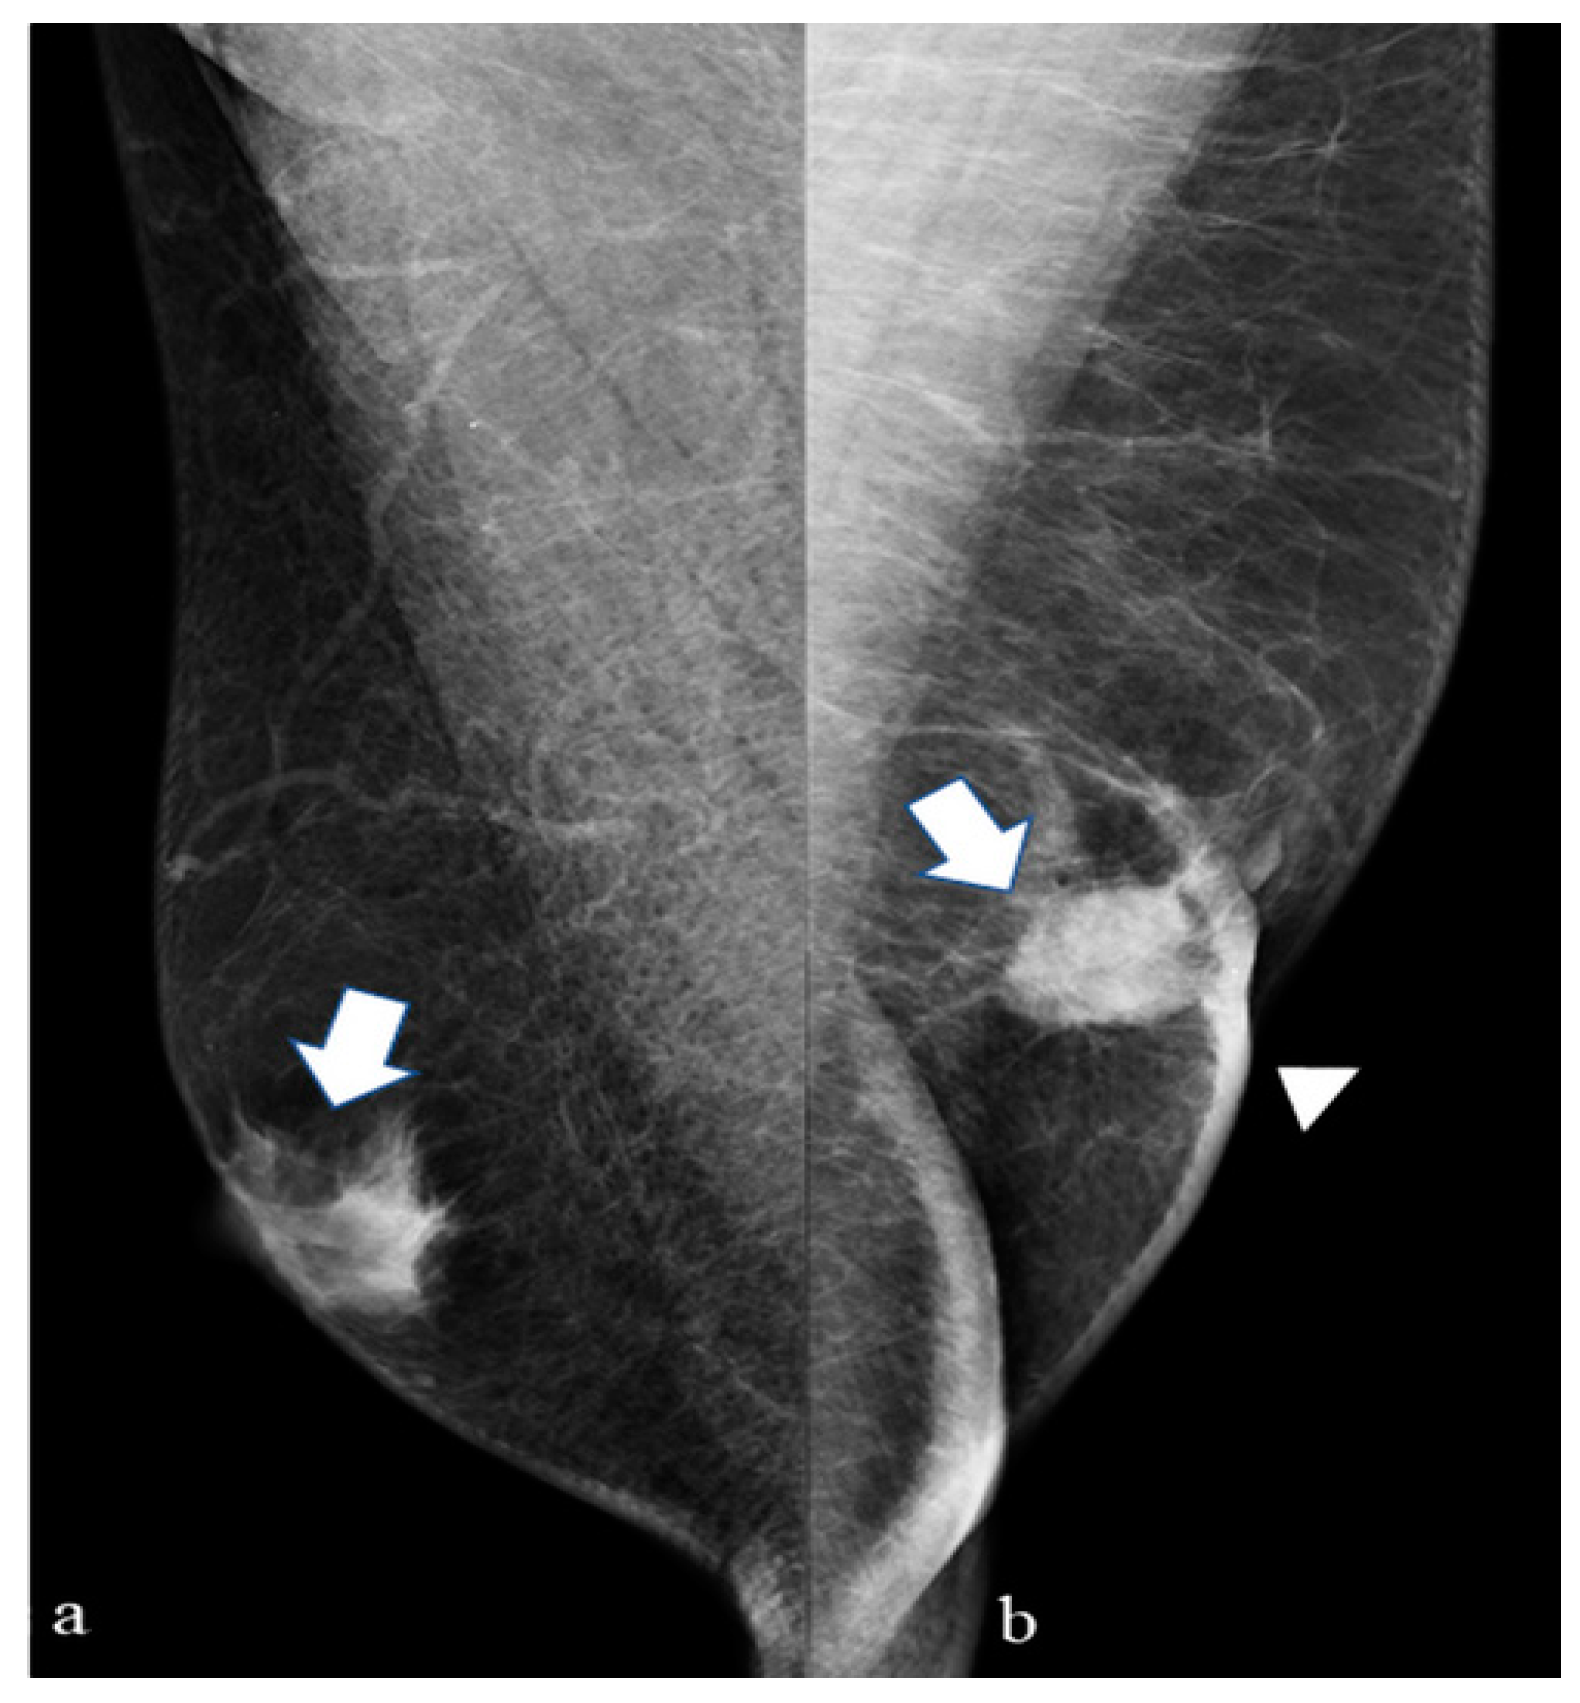

3.2. DM Features

| Type of mammographic lesion, N (%) | Mass | 19 (68) |

| Mass with microcalcifications | 9 (32) | |

| Relation of the mass to the nipple, N (%) | Eccentric | 18 (64) |

| Subareolar | 10 (36) | |

| Shape of the mass, N (%) | Oval | 5 (18) |

| Round | 5 (18) | |

| Spiculated | 18 (64) | |

| Density of the mass, N (%) | Low | 3 (11) |

| High | 25 (89) | |

| Margins of the mass, N (%) | Irregular | 15 (54) |

| Poorly defined | 4 (14) | |

| Regular | 9 (32) | |

| Associated findings, N (%) | No | 20 (71) |

| Nipple retraction | 2 (7) | |

| Skin thickening | 5 (18) | |

| Skin thickening and nipple involvement | 1 (4) |